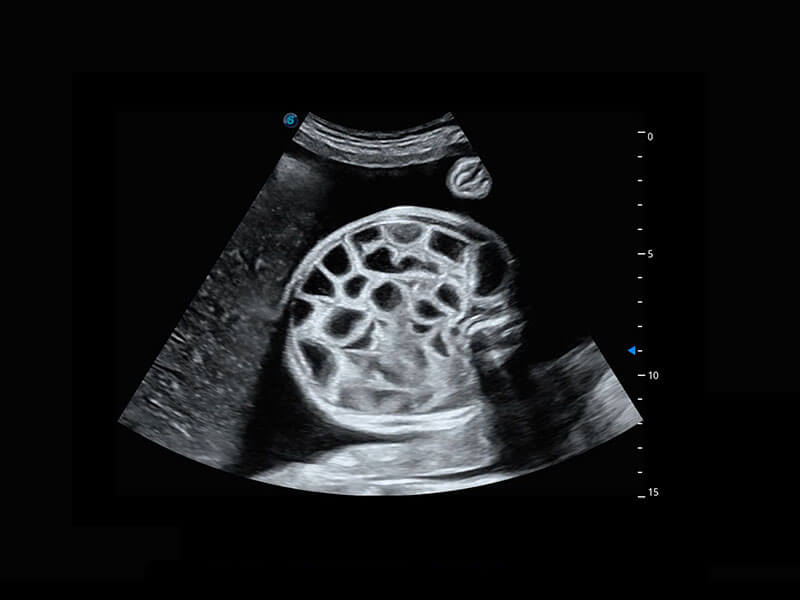

P60优异的图像质量搭载专科探头,在妇科基础疾病的诊断、卵泡生长的监测、输卵管通畅情况的判别等方面为您提供生殖应用方案。

腔内妇科-宫腔分离

腔内妇科-卵巢